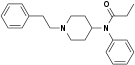

Anilidopiperidines

- 3-Allylfentanyl

- 3-Methylfentanyl

- 3-Methylthiofentanyl

- 4-Phenylfentanyl

- Alfentanil

- α-Methylacetylfentanyl

- α-Methylfentanyl

- α-Methylthiofentanyl

- Benzylfentanyl

- β-hydroxyfentanyl

- β-hydroxythiofentanyl

- β-Methylfentanyl

- Brifentanil

- Butyrfentanyl

- Carfentanil

- Fentanyl

- Lofentanil

- N-Methylcarfentanil

- Mirfentanil

- Ocfentanil

- Ohmefentanyl

- Parafluorofentanyl

- Phenaridine

- R-30490

- Remifentanil

- Sufentanil

- Thenylfentanyl

- Thiofentanyl

- Trefentanil

Structures